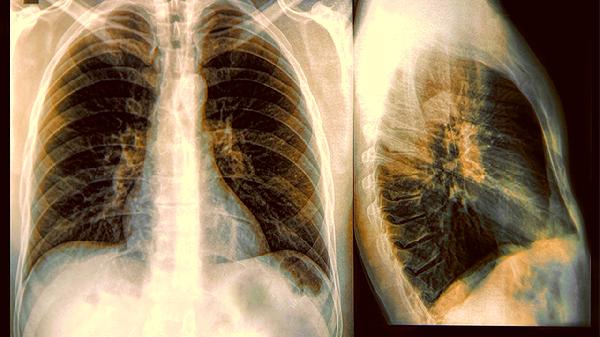

63岁因肺癌走了,常年吃清蒸鱼、炖汤,医生:祸根藏在几个细节里

一位63岁的老人,平时饮食清淡,最爱清蒸鱼和炖汤,却在体检时查出肺癌晚期。家人怎么也想不通,明明吃得这么健康,为何还会得癌?其实,祸根可能就藏在那些被忽略的生活细节里。